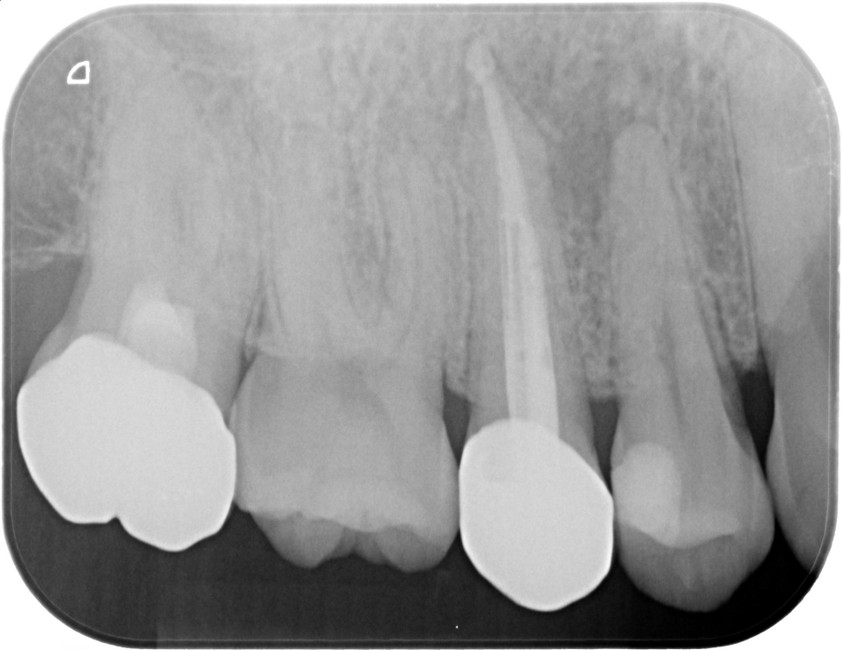

症例4

治療経過

①![]() 術前 |

②![]() 根管治療後3か月経過 |

③![]() 根管治療後1年経過時 |

④![]() 根管治療後2年経過時 |

神経の治療後、①→②→③→④と時間をかけて徐々に治ってくることがあります。

神経の治療は細菌感染を除去する治療です。細菌がいなくなれば、無駄に神経をとらなくても良い歯もあるかもしれません。

| 項目 | 詳細 |

|---|---|

| 患者様データ | 30代 男性 |

| 来院時の主訴 | 「他院で右上の歯3本とも神経をとる必要があると言われた。なんとか神経を残したい。」 |

| 術前検査結果 |

右上第一小臼歯:打診痛(+)・歯髄の生活反応有り 右上第二小臼歯:打診痛(+)・歯髄の生活反応無し 右上第二大臼歯:打診痛(ー)・歯髄の生活反応有り |

| 医院の診断 |

右上第一小臼歯:健全→術前に神経が残せる可能性のある歯と診断 右上第二小臼歯:慢性根尖性歯周炎→術前に神経が残せない歯と診断 右上第二大臼歯:無症候性可逆性歯髄炎→術前に神経が残せる可能性のある歯と診断し、術中に神経を残せると診断 |

| 通院期間 | 2年半 |

| 来院回数 | 10回(定期的なチェック含む) |

| 治療費 | 350,000円(税抜) 《内訳》 右上第二小臼歯:精密根管治療70,000円、ファイバーポストコア20,000円、セラミック治療120,000円 右上第二大臼歯:歯髄温存療法55,000円、セラミック治療85,000円 |

| リスクと副作用 | ①根管治療歯は長期的には破折するリスク ②メインテナンスが必要 |

| ココがこだわりのポイント☝ |

レントゲン検査や患者様の訴える症状だけでは神経を残せるかどうかは断定できません。 この方もレントゲン写真上では神経を残せないように見える歯でしたが、治療前に検査を入念に行うことで残せる可能性を見出すことができました。 同じ悩みを抱えた方は是非お気軽にご相談下さい。 |